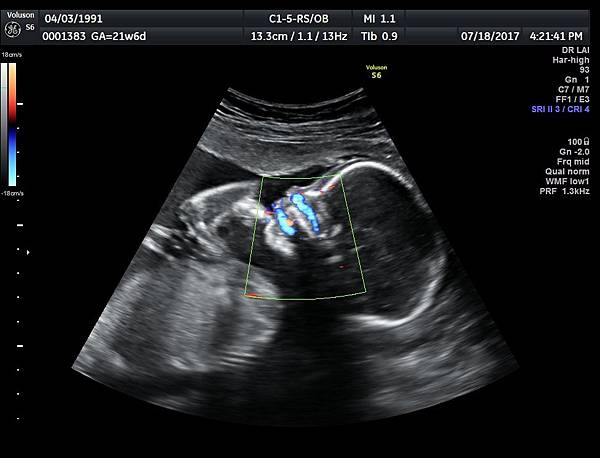

21w 6d right side cleft lip and palate and cleft uvula and brain anomaly < ACC and lissencephaly> images 3421

一個檢查如果要花很長的時間才能完成,這樣的檢查無法變成常規的篩檢方式,我已經在我的診所執行懸雍垂檢查一段時間,我檢查懸雍垂大約30 秒,前提是胎兒的臉最佳位置是側躺,其次是側躺偏向上,我的檢查步驟是上顎(含日後大門牙長出的位置)、舌頭、懸雍垂(= equal sign)(附圖1~8),如果超過60秒無法完成,只有兩個原因,一個是胎兒姿勢不適合或喉嚨羊水空間太小,這時候不要硬碰硬,只要先檢查其他部位,等待時機再回來即可,我的經驗是90%的cases都能順利完成這項檢查(肚皮厚的case真的是很難)。